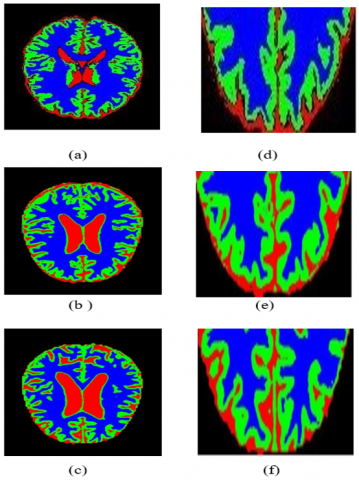

Figure 5 shows the results of the PFCM algorithm applied to segment several brain images. Column 1 presents the original ADNI dataset images, Column 2 shows the extracted CSF regions, Column 3 shows gray matter extraction images, and Column 4 shows white matter extraction for the brain images in the ADNI dataset. Because the image sizes for the ADNI datasets vary significantly, they are resized to 512×640 pixels as part of the pre-processing step. The post-processing step involves converting the final segmented regions to black and white to facilitate comparison with the ground truth.

The segmentation results of the proposed algorithm are shown in Figure 6. Row 1 illustrates the ground truth for gray matter, white matter, and CSF. Row 2 shows GM, WM, and CSF extraction using PFCM, while Row 3 shows the same extraction method using GRIFCM. According to a subjective evaluation, the proposed method effectively extracts brain tissue. The segmentation results of the proposed algorithm are displayed in Figure 7. Based on subjective evaluation, the proposed method proves effective for brain tissue extraction.

Figure 5. (a) very mild (e) mild (i) moderate images from ADNI data set, (b)(f)(j) CSF extracted, (c)(g)(k) gray matter extracted (d)(h)(l) white matter extracted

Figure 6. Segmentation results of proposed algorithm (row 1) ground truths of GM, WM, and CSF, (row 2) GM, WM, and CSF extracted using PFCM (row 3) GM, WM, and CSF extracted using GRIFCM [14]

Figure 7. Segmentation results of proposed algorithm PFCM for normal, moderate, and mild Alzheimer's images